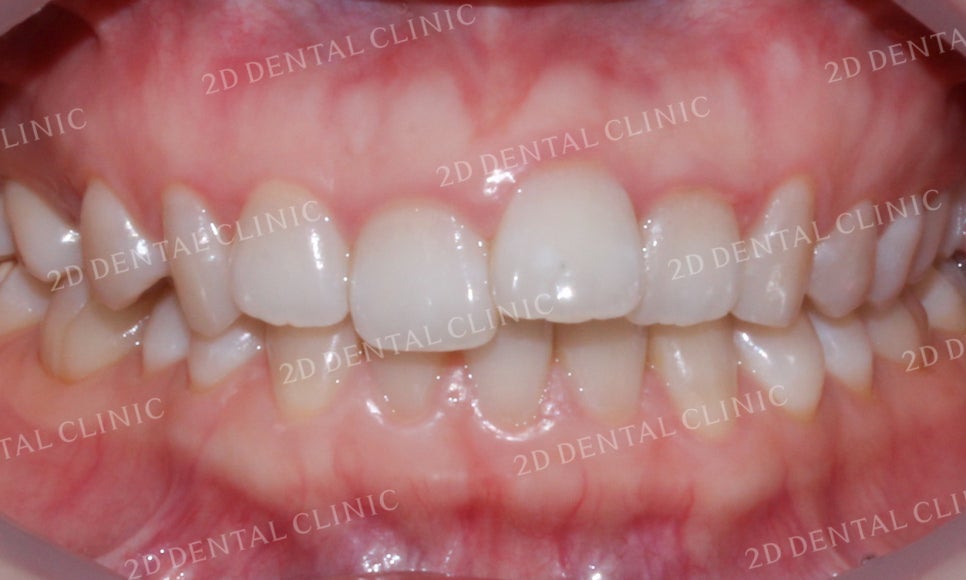

치아 교합 시 입술의 모습입니다.

중절치의 덧니 교정 전 윗입술에서

미세하게 돌출감이 느껴졌었는데요,

교정 후 튀어나온 부분 없이

돌출감이 사라진 모습입니다.

미소 시 전치부 모습입니다.

덧니 증상으로 인해 순측으로

뻐드러지게 나와있던

좌측 중절치가 덧니 교정 후

제자리를 찾은 모습입니다.